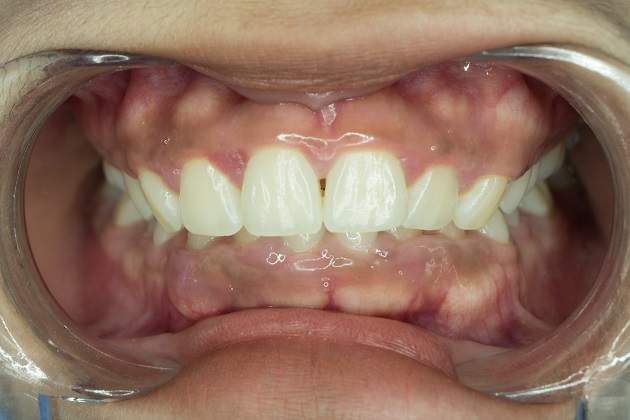

Фотографии до и после коррекции глубокого прикуса

— Пациентка обратилась с проблемами, связанными с неправильным положением зубов и неудовлетворительной эстетикой. В лечении использовались только брекеты, и общий срок терапии составил один год.